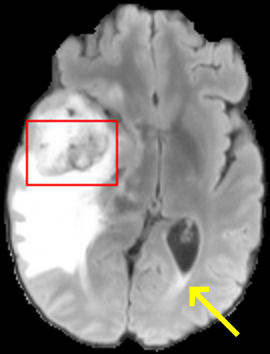

To test the impact of the iterative refinement on YODA’s translation quality, we compared regression and diffusion sampling on the RS data and present additional generation examples in Fig. 6. We observe that diffusion sampling visually resembles the appearance of the acquired images. Regression sampling preserves key anatomical features – the GM/WM boundary, WMHs (Fig. 4), the outline of the pallidum (Fig. 6) – but omits many high-frequency features. To investigate whether iterative refinement during diffusion sampling adds relevant and systematic medical information or only imitates acquisition noise, we performed ExpA sampling, i.e. averaging the output of several ( or ) diffusion trajectories. We observed a gradual loss of high-frequency details when increasing the (see also the supplementary video), indicating that the effect of the iterative refinement is non-systematic. For , the images are visually almost indistinguishable from the initial regression solution (see the supplementary video, and Fig.4 and 6). We directly compared the synthesis results of ExpA () and regression sampling quantitatively and found the differences to be minimal (SSIM: 99.73%, PSNR: 45.30 dB), i.e. diffusion sampling approaches the initial regression solution for a high . The quantitative analysis of the image quality (Tab. 1) showed that diffusion sampling impairs the assessed SSIM and PSNR in comparison to regression sampling for both the in- and external test sets, which we attribute to noise generation (Sec. 3.1). In turn, ExpA averages improved both metrics and, for , performed mostly on par with the regression solution in both test sets in terms of SSIM, while the PSNR in the RS was slightly increased (Tab. 1). However, we observed that ExpA sampling YODA improves the replication of systematic 3D low-frequency image intensity drifts (bias fields) due to the 3D synchronization in 2.5D diffusion sampling. Yet, this apparent advantage did not generalize to the external MBB dataset, as bias fields are MR protocol-specific.

We evaluated the impact of the proposed sampling methods on the performance of the independent, externally trained SHIVA-WMH tool as compared to manual reference labels (Tab. 1). Smoother images (higher or from regression sampling) yielded improved performance over those from diffusion sampling.

To assess the suitability of YODA-generated images for WMH detection independent of segmentation tools, we also calculated the CNR (15) of WMHs. This confirmed that the contrast of WMHs is preserved in the regression images, whereas we noted slightly reduced WMH contrast for diffusion and ExpA-sampled images (Tab. 1).

When analyzing the RS synthesis results (Fig. 4), we noted that most reference methods strive to imitate realistic images, but several artifacts can be observed such as hallucinated WMHs (SynDiff) and salt-and-pepper noise (SynDiff, I2I-Mamba, ResViT).